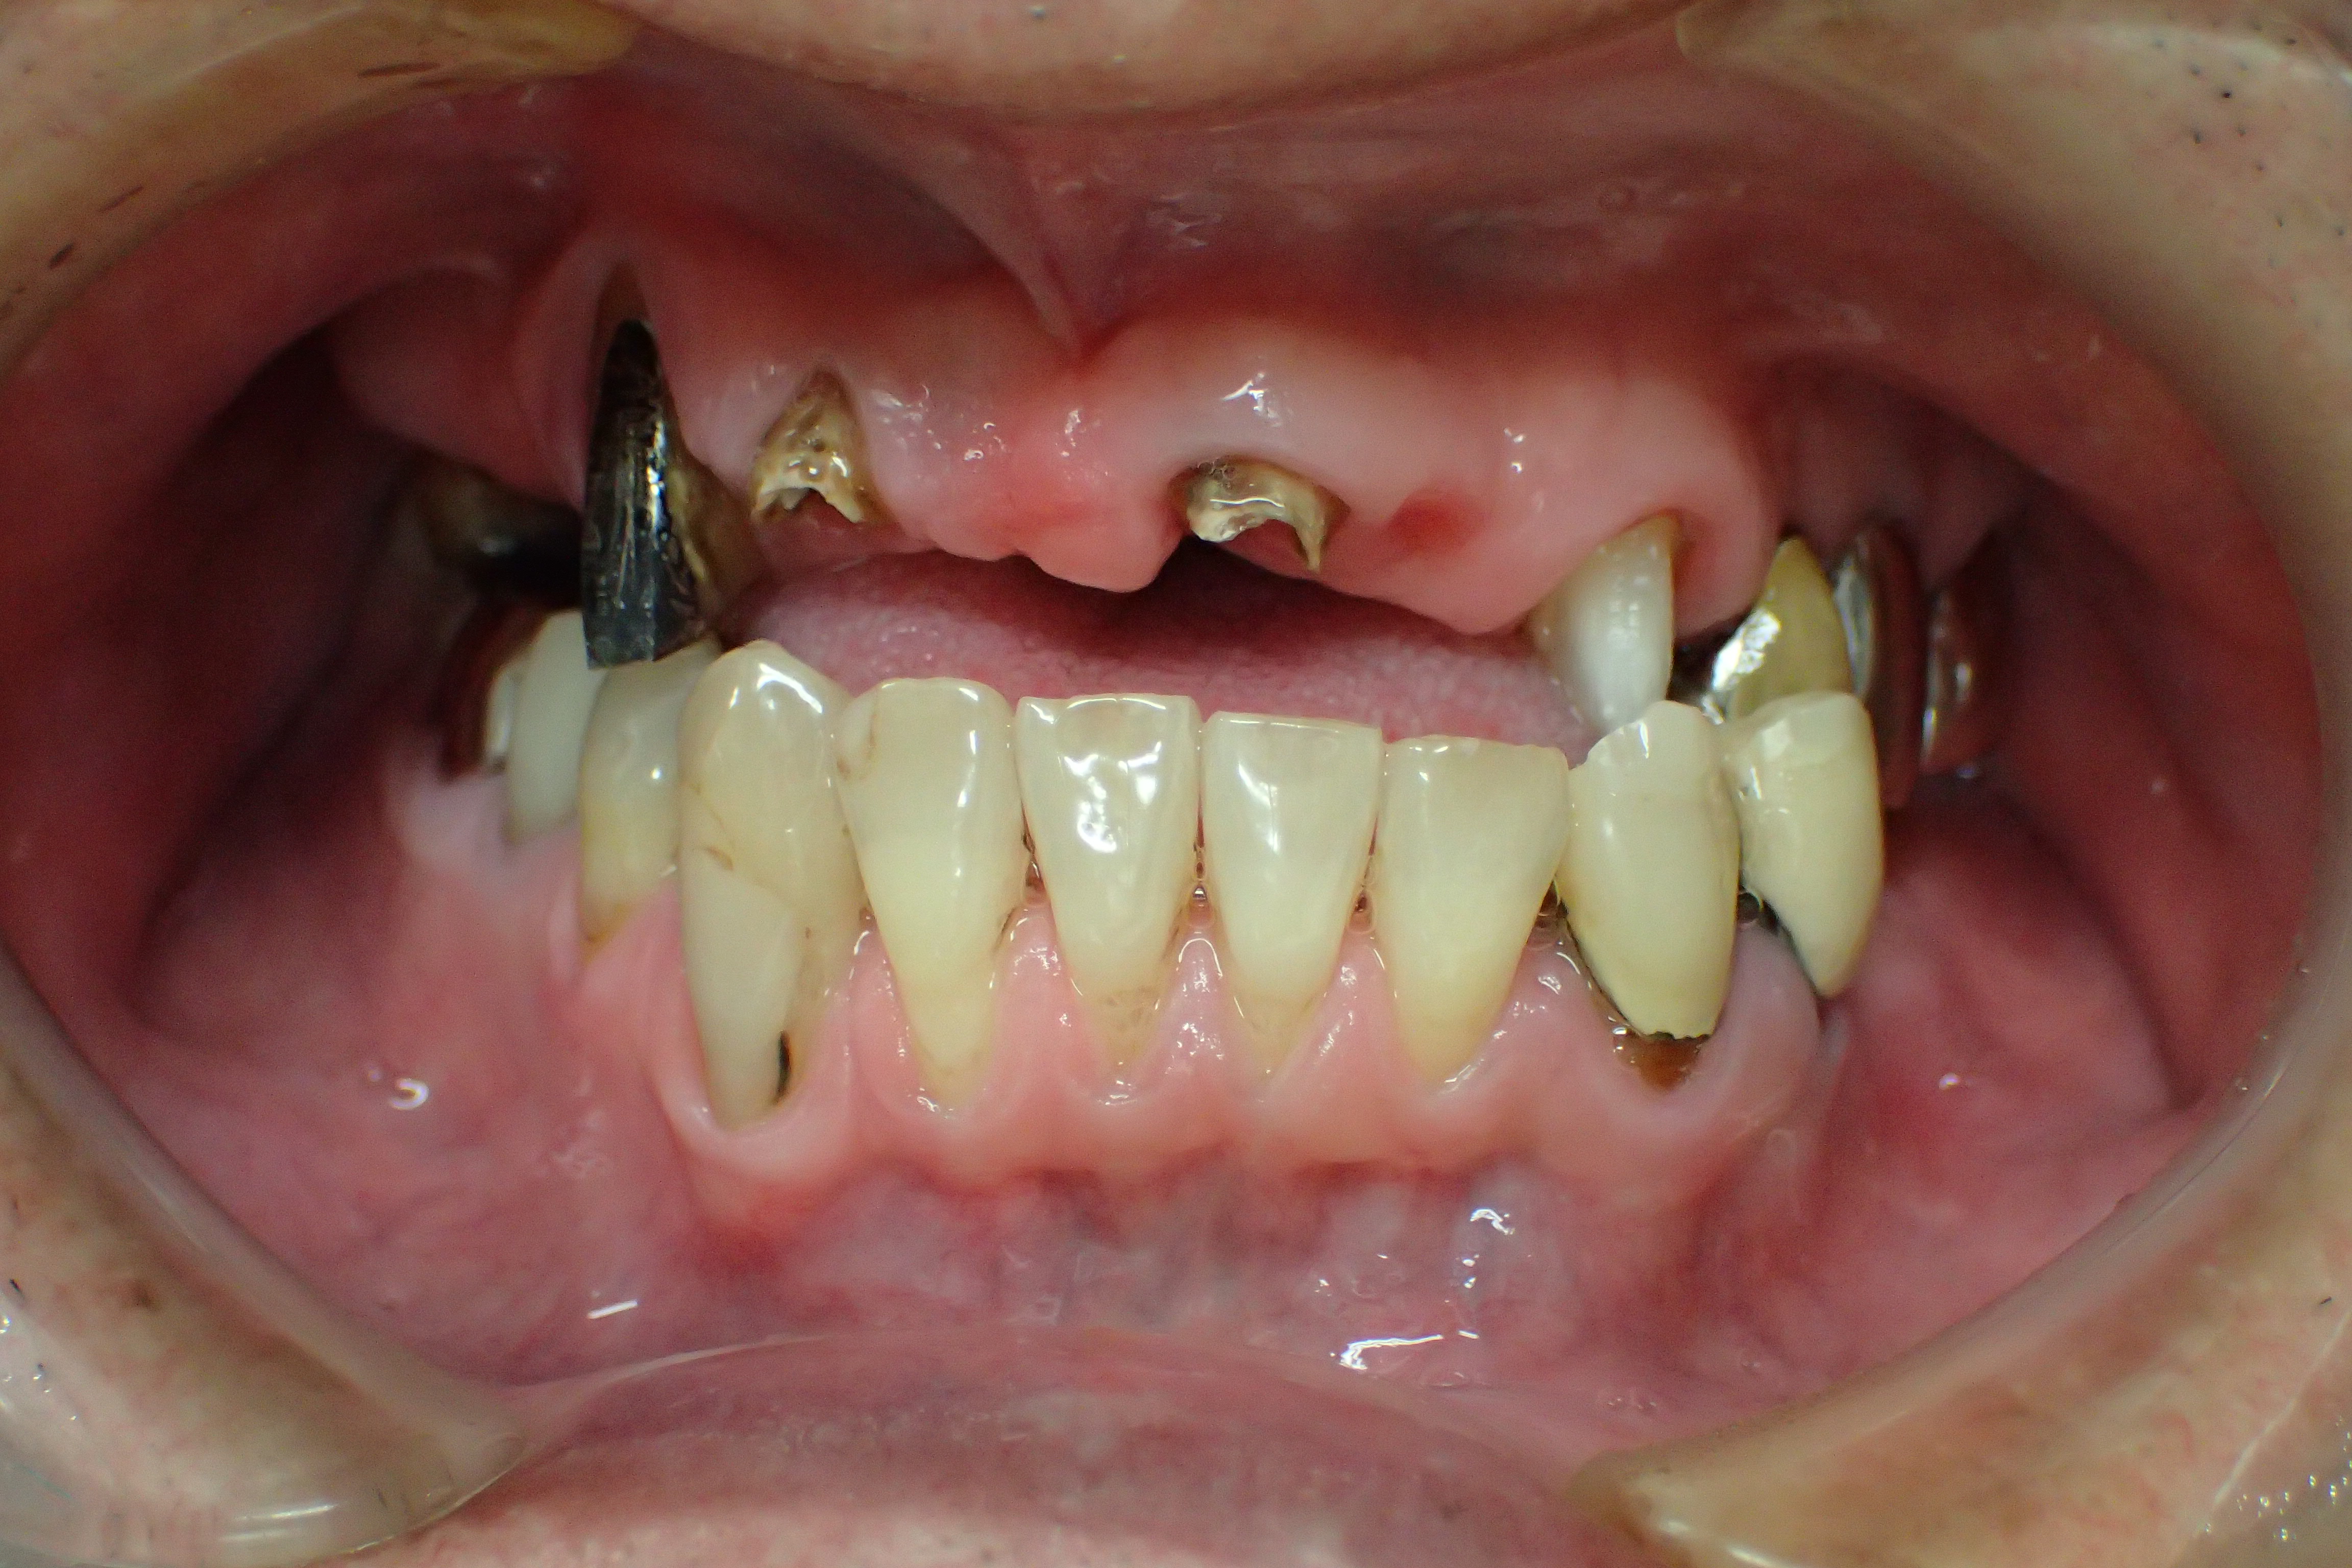

インプラント施術前

下あごの奥歯がなく、食いしばりが強いため前歯もすり減ってしまいました。

インプラント施術後

インプラントを6本埋入してかみ合わせも適当な高さに改善、前歯もセラミックをかぶせて見た目も改善しました。